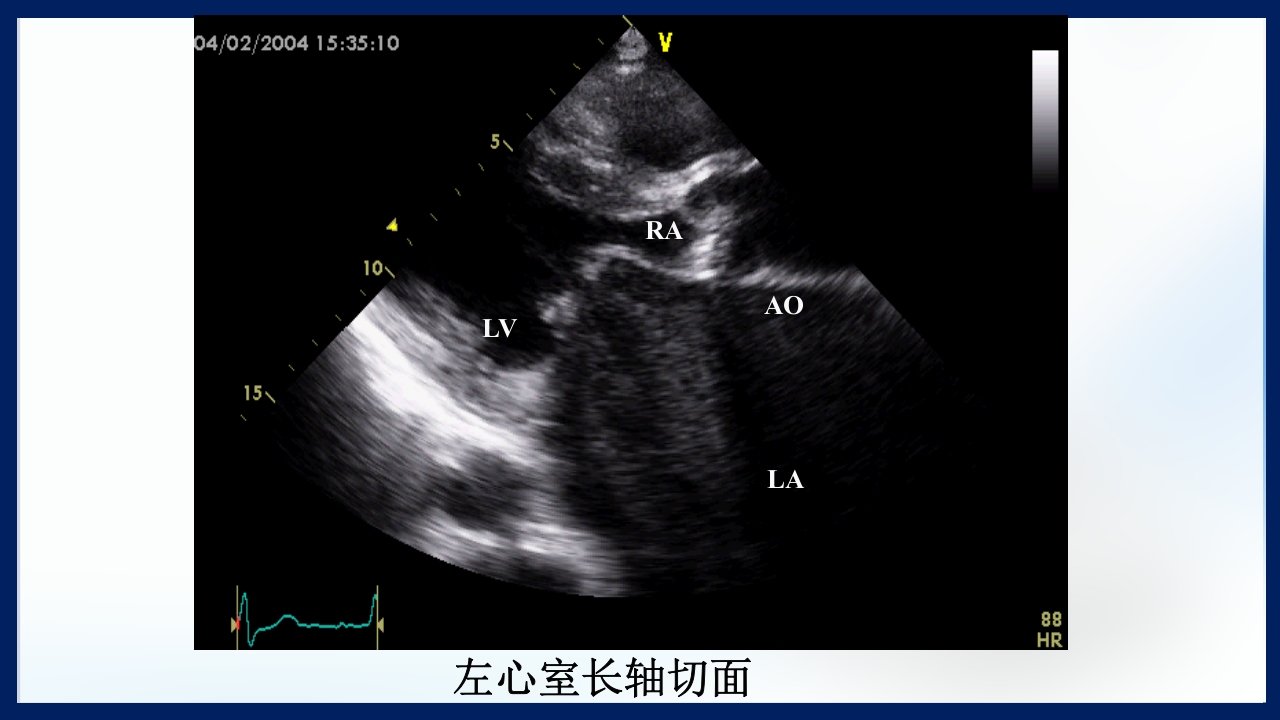

心 脏 瓣膜 医师:XXX 日期:20XX.XX.XX 讲授目的和要求 1 掌握二尖瓣和主动脉瓣膜病变的病理生理、临床表现及诊断方法。 熟悉二尖瓣和主动脉瓣膜病变的病因、鉴别诊断、并发症、治疗原则及 2 手术适应证。 3 了解瓣膜病的检查方法及治疗新进展。 心脏瓣膜病 是由于炎症、粘液样变性、退行性改变等原 因引起的单个或多个瓣膜结构的功能或结构异常,导致 瓣口狭窄及(或)关闭不全。二尖瓣最常受累,其次为 主动脉瓣。 (Rheumatic Heart Disease)简称风心病, 是风湿性炎症过程所致瓣膜损害,主要累及40岁以下人 群。 瓣膜粘液样变性和老年瓣膜钙化所致瓣膜病日渐增多。 3 瓣膜病分类 按病因分类: 风湿性、老年退行性、先天性、相对性 按受累部位和类型分: 二尖瓣狭窄、二尖瓣关闭...